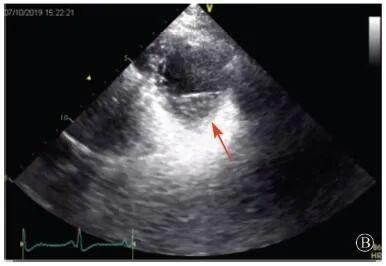

A:胸骨旁长轴平面,左室舒张末内径略增大,室壁无明显增厚;

B:胸骨旁左室短轴切面心尖水平,可见心肌肌小梁增多,其内可见隐窝(箭头所示)

图3 患者入院后超声心动图